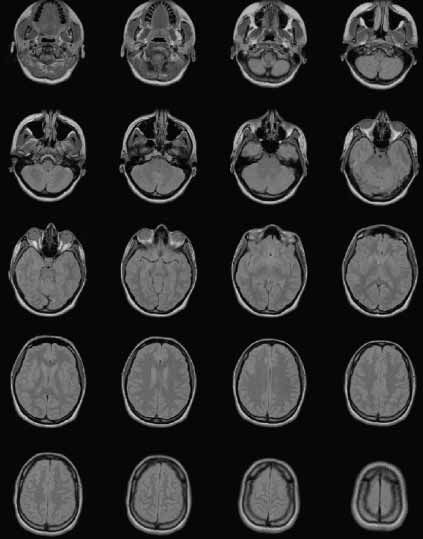

In medical imaging, a patient is subject to an imaging study, which may contain multiple series of images. Each series is performed on a single modality such as an MR, CT, or X-ray device and can have multiple related images. Suppose that we have a study consisting of a series of 20 transverse MRI brain images and we want to read them into MATLAB. (These 20 images are stored in 20 DICOM files with names such as brain_017.dcm, which you can download from MATLAB Central if you want to run the examples.) Let's suppose we know that each image is 256-by-256 and contains signed 16-bit data. We can read the series with the following code:

After running this code, the MATLAB workspace contains a 4-D array with the image data, and a plot of the MR slices appears.

You can use MATLAB and the Image Processing Toolbox to perform multiple tasks with this data. For example, MATLAB provides sophisticated volume visualization techniques to reconstruct a 3-D surface from these slices and then apply surface and lighting effects. The example in the Help section for the isocaps function shows this implemented. The imtransform and tformarray functions in the Image Processing Toolbox make it easy to extract slices in different orientations from the transverse data. For example, the "Extracting Slices from a 3-Dimensional MRI Data Set" example shows how to extract saggital slices from a similar dataset. You can also use the morphology functions within the Image Processing Toolbox to perform operations such as image segmentation, feature extraction, and image statistics. Alternatively, you can write your own functions to perform volume estimation, shrinkwrapping, etc.